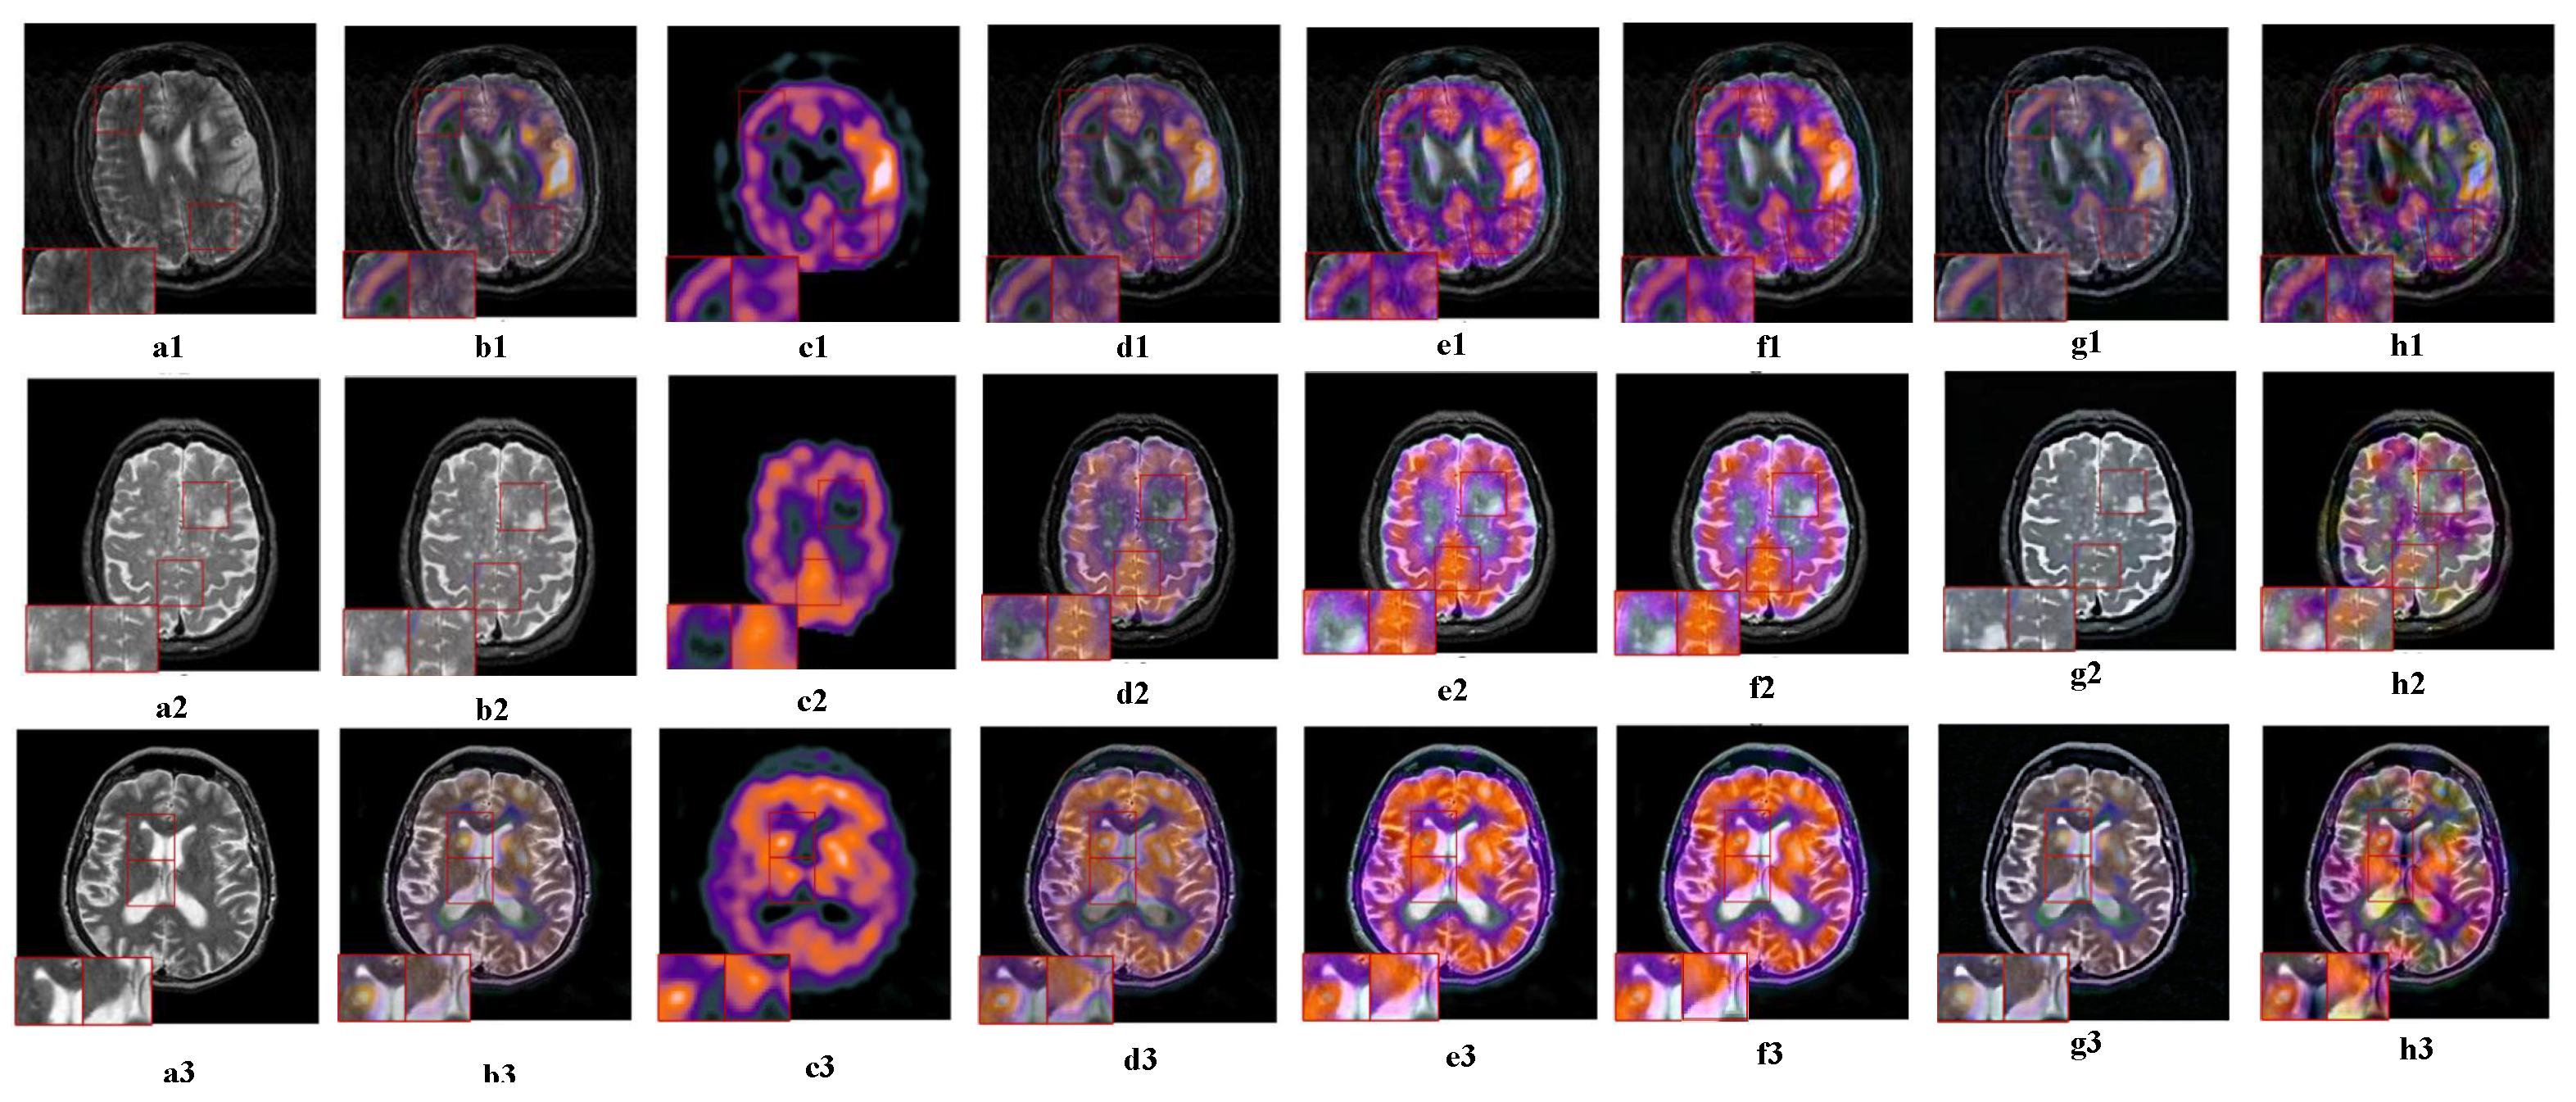

5.2.5. Fusion Analysis on MR-SPECT